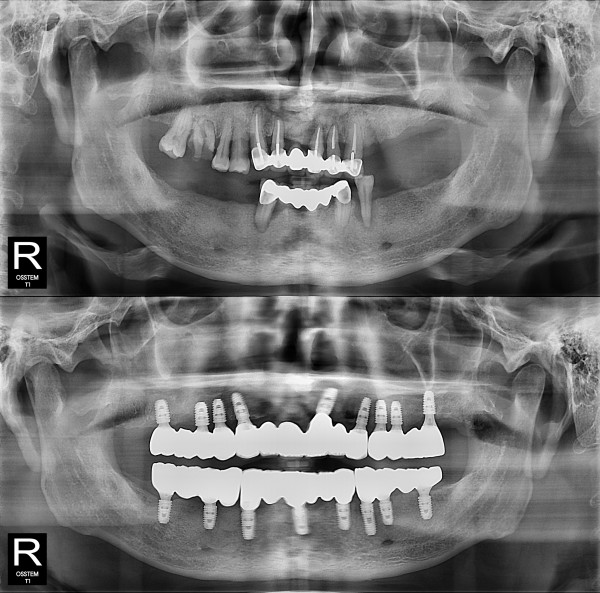

种植牙

全口种植牙